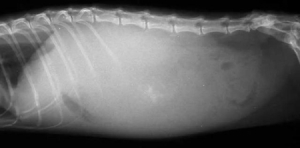

腹水究竟是什么?腹水指腹腔内蓄积非生理性液体 水和淋巴液,也称为腹腔积液,属于一种继发性疾病。

幼年犬和老年犬容易出现,菜叶说说,典型的表现为腹围增大、腰背凹陷。

腹水,归根到底还是一种“水”,所以和狗狗肥胖或者怀孕有明显的区别。

腹水如何做诊断?腹水的诊断并不难,难点在原发病因的寻找,往往都需要大量的检查,这意味着检查费用会比较高。

比较有价值且性价比较高的检查包括:血常规、生化、尿检、X光片、超声 腹超、心超、胰腺炎检测等,其他检查可以根据具体情况进行选择 腹水液体成分评估、胆汁酸检测、活检等。